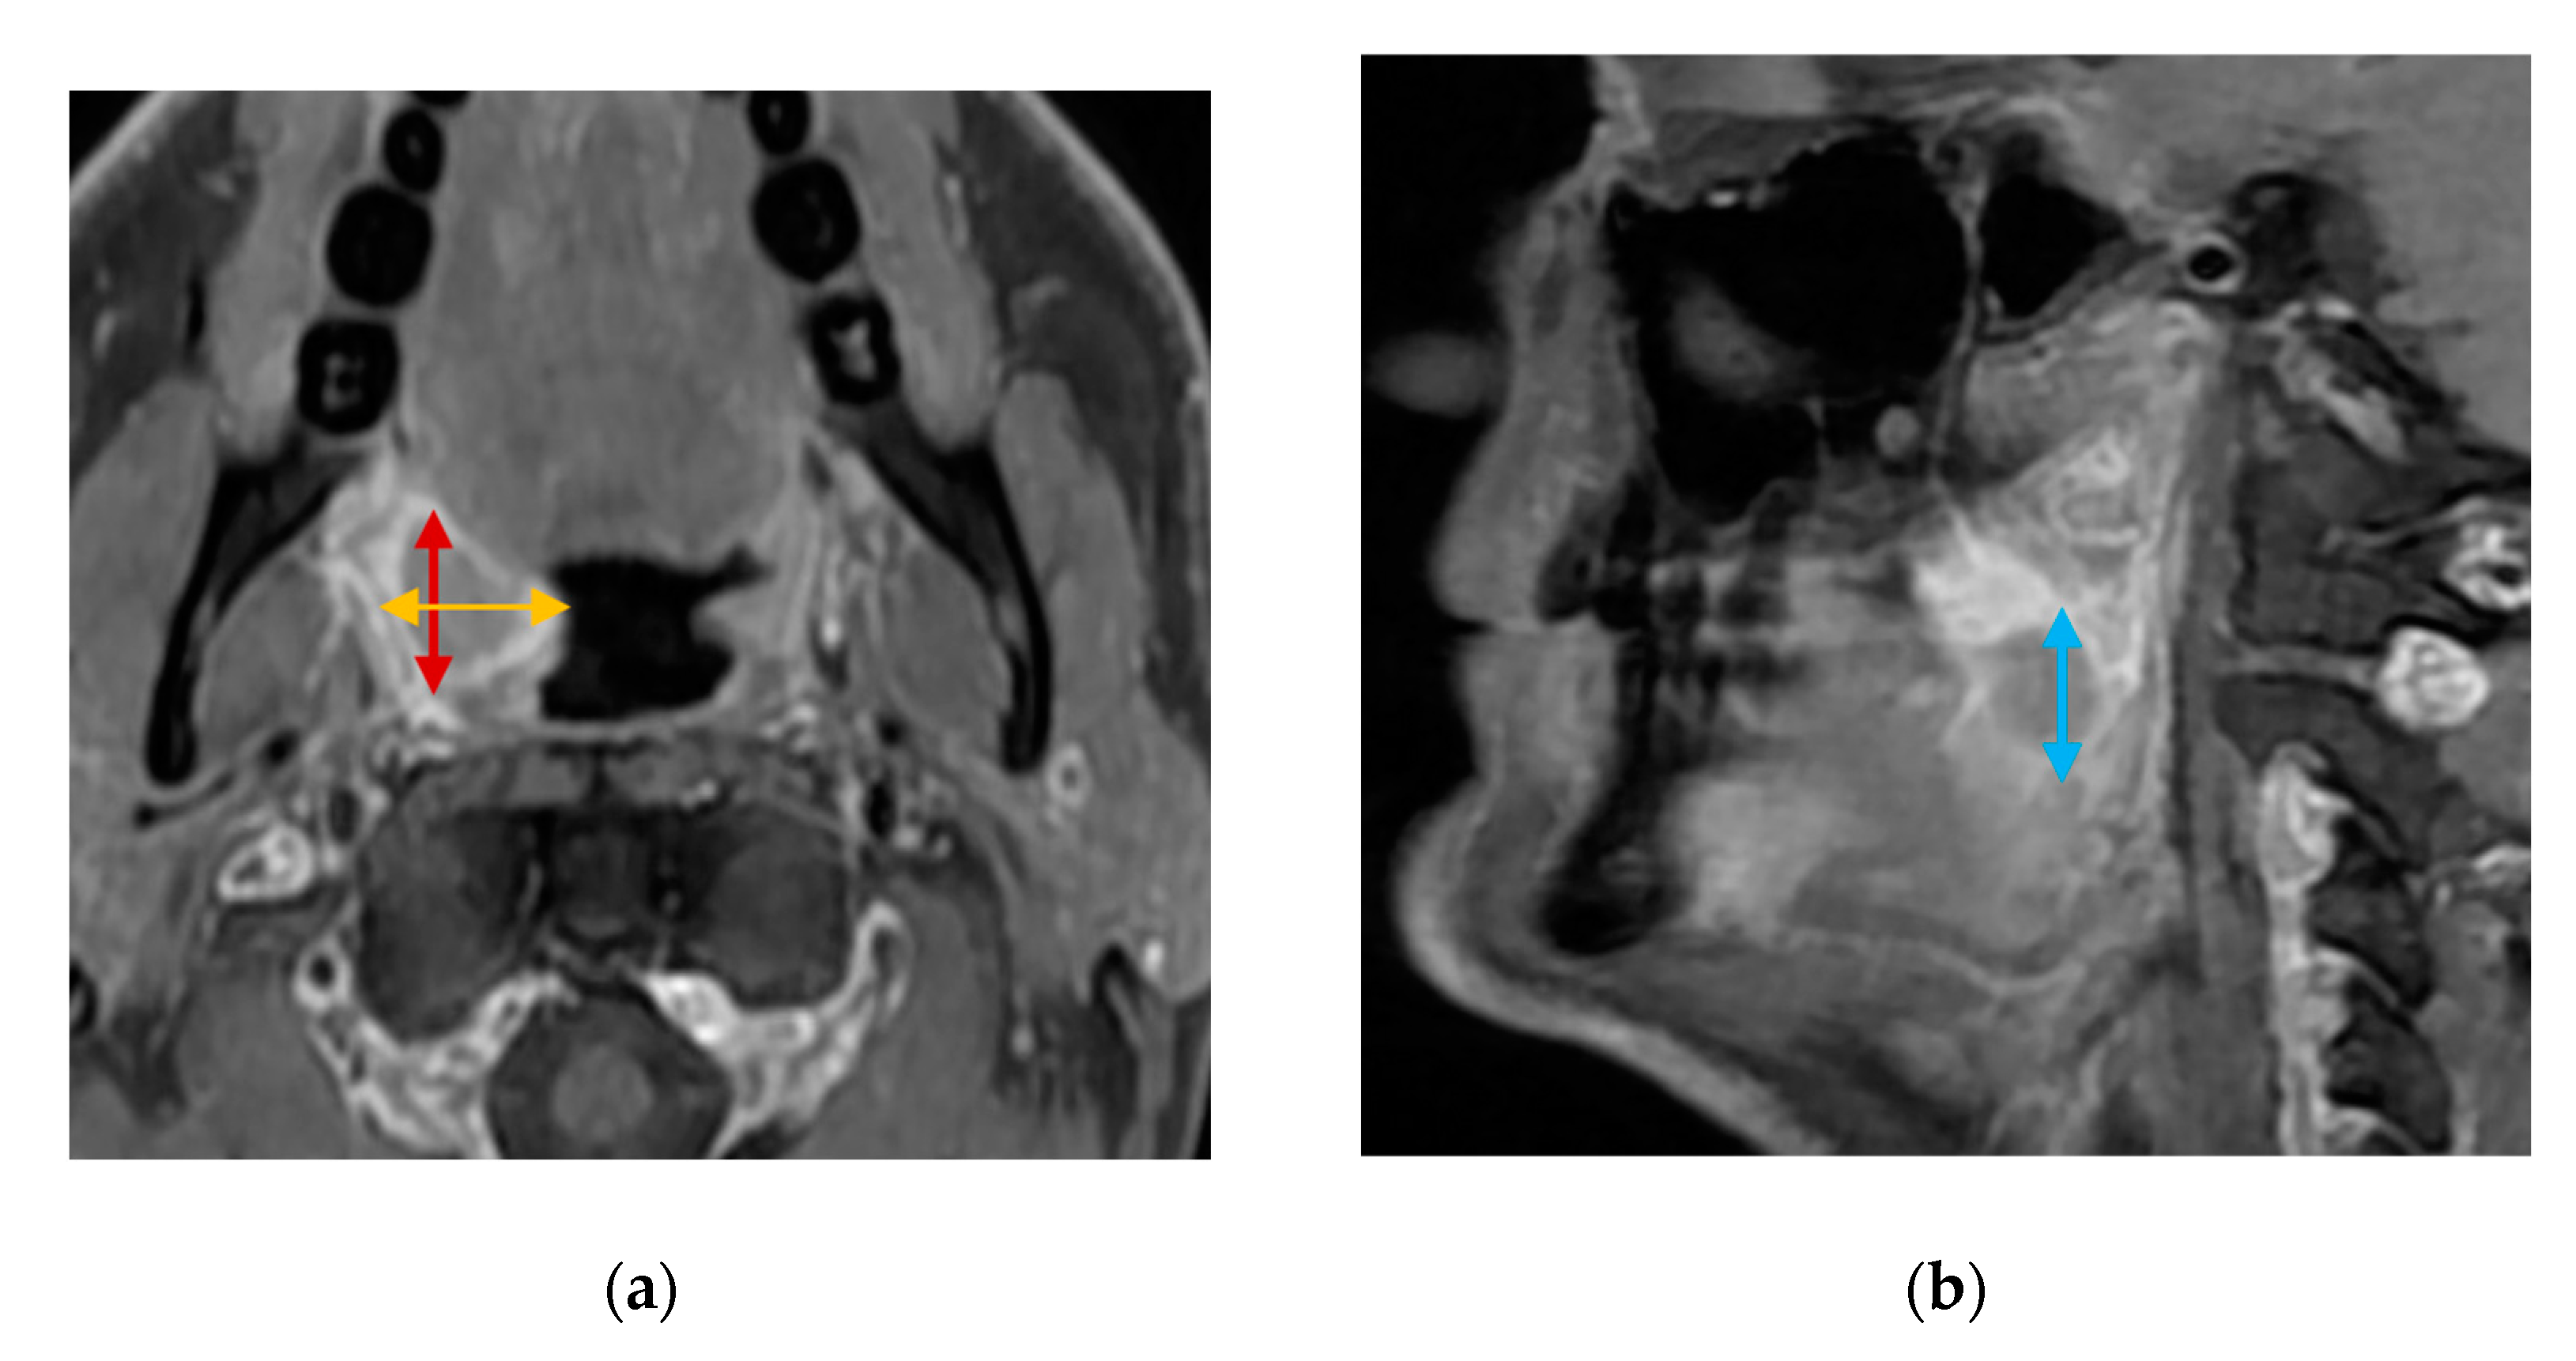

2.4. Cross-Sectional Imaging (Comparison Tests)

- Tumor detection, size (mm) in three dimensions (craniocaudal, anteroposterior, and mediolateral), and volume (mm3) estimated clinically via US, MRI, CT, and histopathology.

- Categorical T-stage (Tx, T0, T1, T2, T3, or T4) measured clinically via US, MRI, and CT.